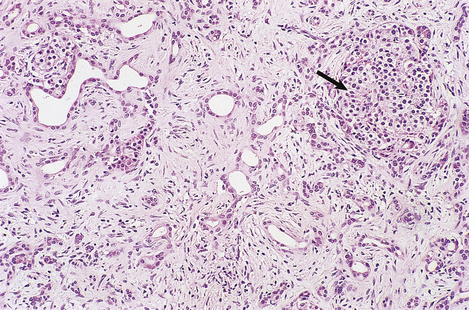

Although the pathogenesis of the liver cell damage resulting from HAV and HBV infection is different, the changes in the liver in a typical case are very similar (Fig. 16.5). The principal features are:

image

Fig. 16.5 Liver histology in acute viral hepatitis. There is disarray of the liver cell plates, accompanied by an inflammatory infiltrate and liver cell apoptosis (arrowed).

The swelling of liver cells, portal oedema and the infiltration by inflammatory cells are responsible for hepatomegaly in viral hepatitis.